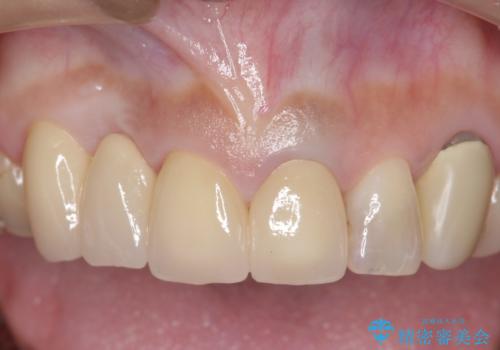

オールセラミッククラウン 下がってしまった前歯の歯茎の改善

- 他院で治療したところ、右上2番目の歯の歯茎が下がってしまったので診て欲しいといらっしゃった方の症例です。

診査の結果右上2は歯根が破折しており、それが原因で骨及び歯肉の吸収が起きていました。

このまま右上2の抜歯を行うとさらに歯茎が下がる恐れがあったため、歯の挺出によって骨レベルを回復した上で抜歯し、歯槽堤保存術(抜歯窩に人工骨を填入する手術)を行いました。

その後ブリッジによる補綴を行うことで、自然な見た目を再現することができました。